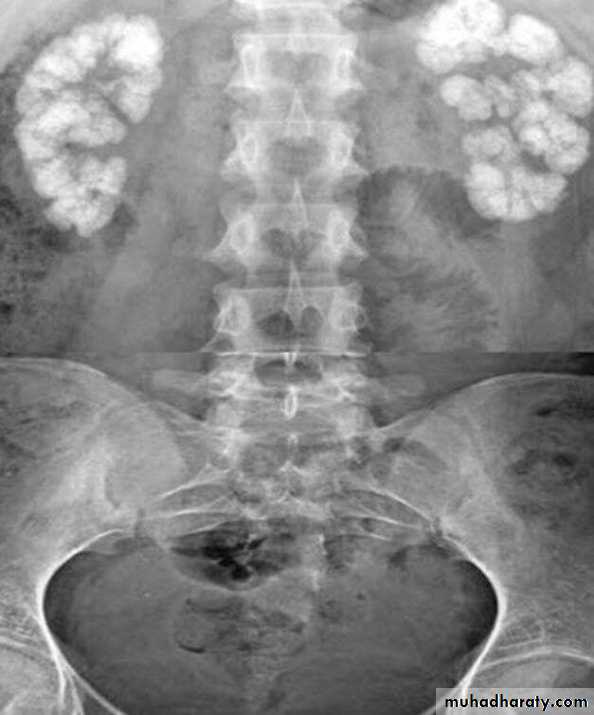

70- 80 % are calcified and show varying densities on plain film

The larger stone assume the shape of the PCS staghorn calculus

Plain film exam of the urinary tract ( KUB) is more sensitive than US for detecting opaque renal and ureteric stone .Plain film is essential to be used as a preliminary film before injection of the contrast in IVU and should be examined carefully because even a large stone can be hidden within the opacified collecting system once contrast medium has been given.